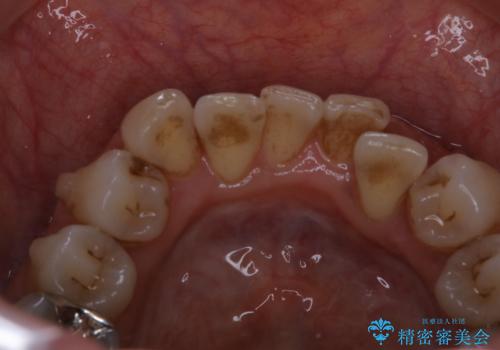

インビザラインの治療中の患者様のクリーニング前後写真です。

- インビザラインの矯正治療中に歯石や着色(ステイン)が付着してしまっていたため、歯科衛生士による専門的クリーニングを行いました。

今回はお口全体に歯石や着色(ステイン)が付着していたため、自費のPMTC(クリーニング)60分コースをご案内し、徹底的に除去しました。